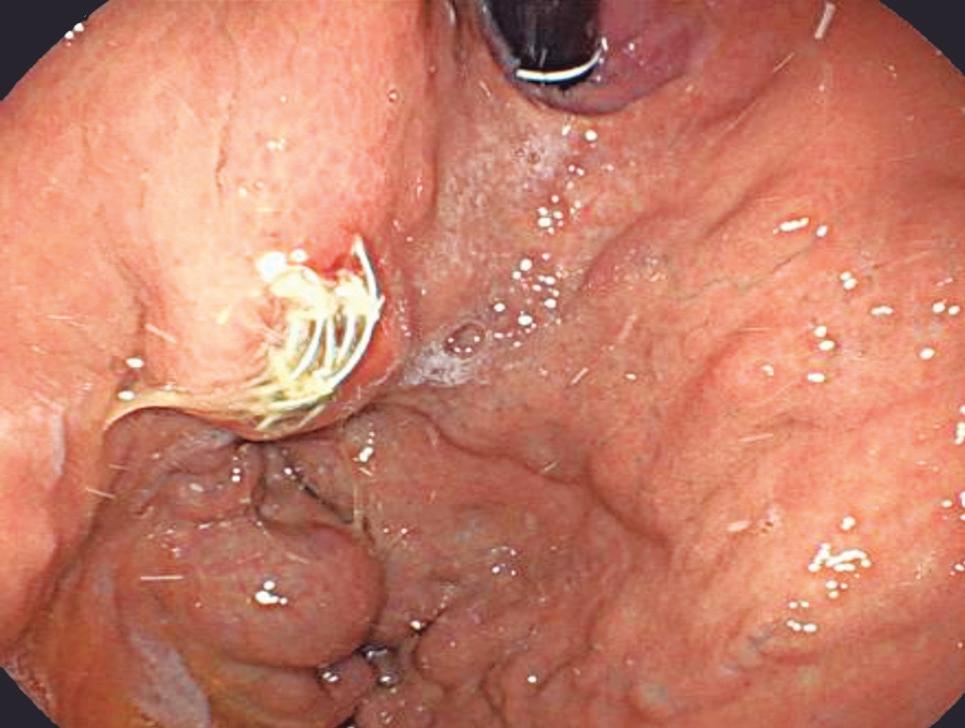

Evaluación endoscópica e histológica

La endoscopía superior es un procedimiento fundamental para el diagnóstico, la evaluación de la respuesta al tratamiento y el monitoreo a largo plazo de la actividad de la EEo. Los hallazgos endoscópicos típicos incluyen edema (reducción de vascularidad), anillos esofágicos fijos, exudados blancos, surcos longitudinales, estenosis, estrechamiento de la luz esofágica, friabilidad de la mucosa (mucosa en papel crepé) y una consistencia firme de la mucosa al realizar biopsias (signo de “tracción" o "resistencia”) en pacientes con fibrosis (Figura 1). Estos hallazgos no son patognomónicos y no constituyen un criterio diagnóstico; sin embargo, cuando se evalúa de forma cuidadosa, en la gran mayoría de los casos se pueden observar.19-21

Es imperativo llevar a cabo una exploración endoscópica minuciosa en todos los casos de sospecha de patología esofágica. En el contexto de la EEo, esto requiere dedicar un tiempo adecuado a la visualización completa del esófago tras la intubación, evitando desplazar o raspar los exudados, insuflando adecuadamente el esófago, eliminando cuidadosamente mucosidad, saliva o detritus, y evaluando el calibre esofágico. Esta evaluación puede incluir la retroflexión en la unión gastroesofágica para estimar el diámetro de las estenosis en dicha región.22

En el panel A se observa un esófago con edema difuso y pliegues longitudinales; en el panel B se aprecia edema con pliegues y exudados blanquecinos; en el panel C se evidencia un estrechamiento luminal acompañado de anillos esofágicos y exudados; y en el panel D se muestra un desgarro mucoso posterior a la dilatación con bujía de Savary, hallazgo esperado tras este procedimiento terapéutico.

Figura 1. Características endoscópicas de la esofagitis eosinofílica